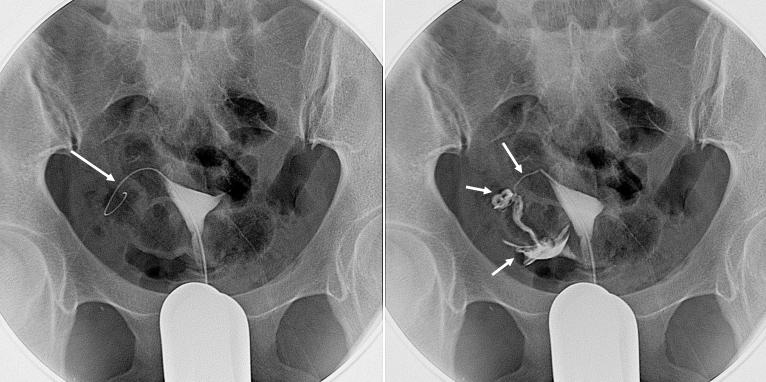

输卵管再通术进行中,右侧再通成功

首先,医生会经过严格的清洁消毒,从阴道向子宫腔送入介入治疗器械,在电视透视下进行子宫和输卵管造影;明确阻塞部位后,就要送入纤细光滑、具有一定刚度和柔软度的导丝对阻塞处进行反复轻柔的机械疏通。再次造影确认再通成功后,应经导管向输卵管内注入输卵管疏通液,以加强治疗效果并防止再闭塞。一侧成功后,同法再进行另一侧治疗。

输卵管再通术进行中,左侧再通成功

是不是很简单?的确,原理很简单,效果却比较可靠,经验丰富的介入医生可使再通成功率达到90%以上。但要注意,如果轻视训练,粗暴进行,纤细的输卵管也可能造成损伤,手术也就会失败。